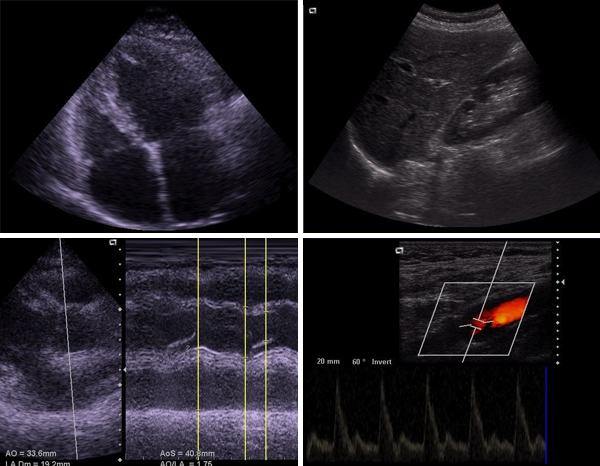

Ultraschall

Mit dem Ultraschall können nicht nur einfach und risikolos Innere Organe dargestellt werden, mit dem sogenannten Farbduplex-Ultraschall werden auch Blutflüsse in Arterien, Venen und im Herzen sichtbar gemacht.

UltraschallBilder